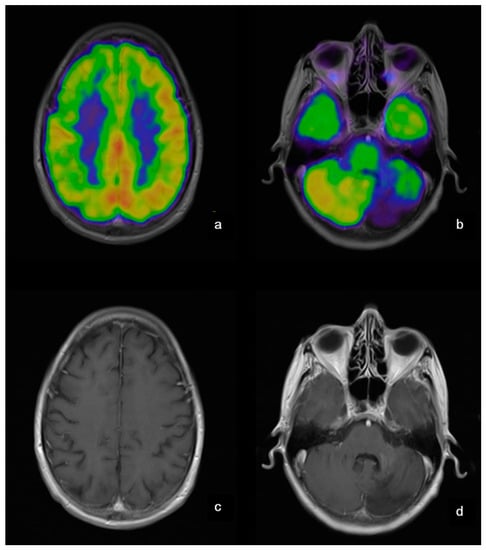

- Werner, P.; Saur, D.; Zeisig, V.; Ettrich, B.; Patt, M.; Sattler, B.; Jochimsen, T.; Lobsien, D.; Meyer, P.M.; Bergh, F.T.; et al. Simultaneous PET/MRI in stroke: A case series. J. Cereb. Blood Flow Metab. 2015, 35, 1421–1425. [Google Scholar] [CrossRef] [PubMed]

| 10 | 18FDG | PET/MRI | Record the relative values of regional cerebral glucose metabolic rate in Fabry disease and monitoring dementia | Korsholm et al. [30], Jena et al. [31] |